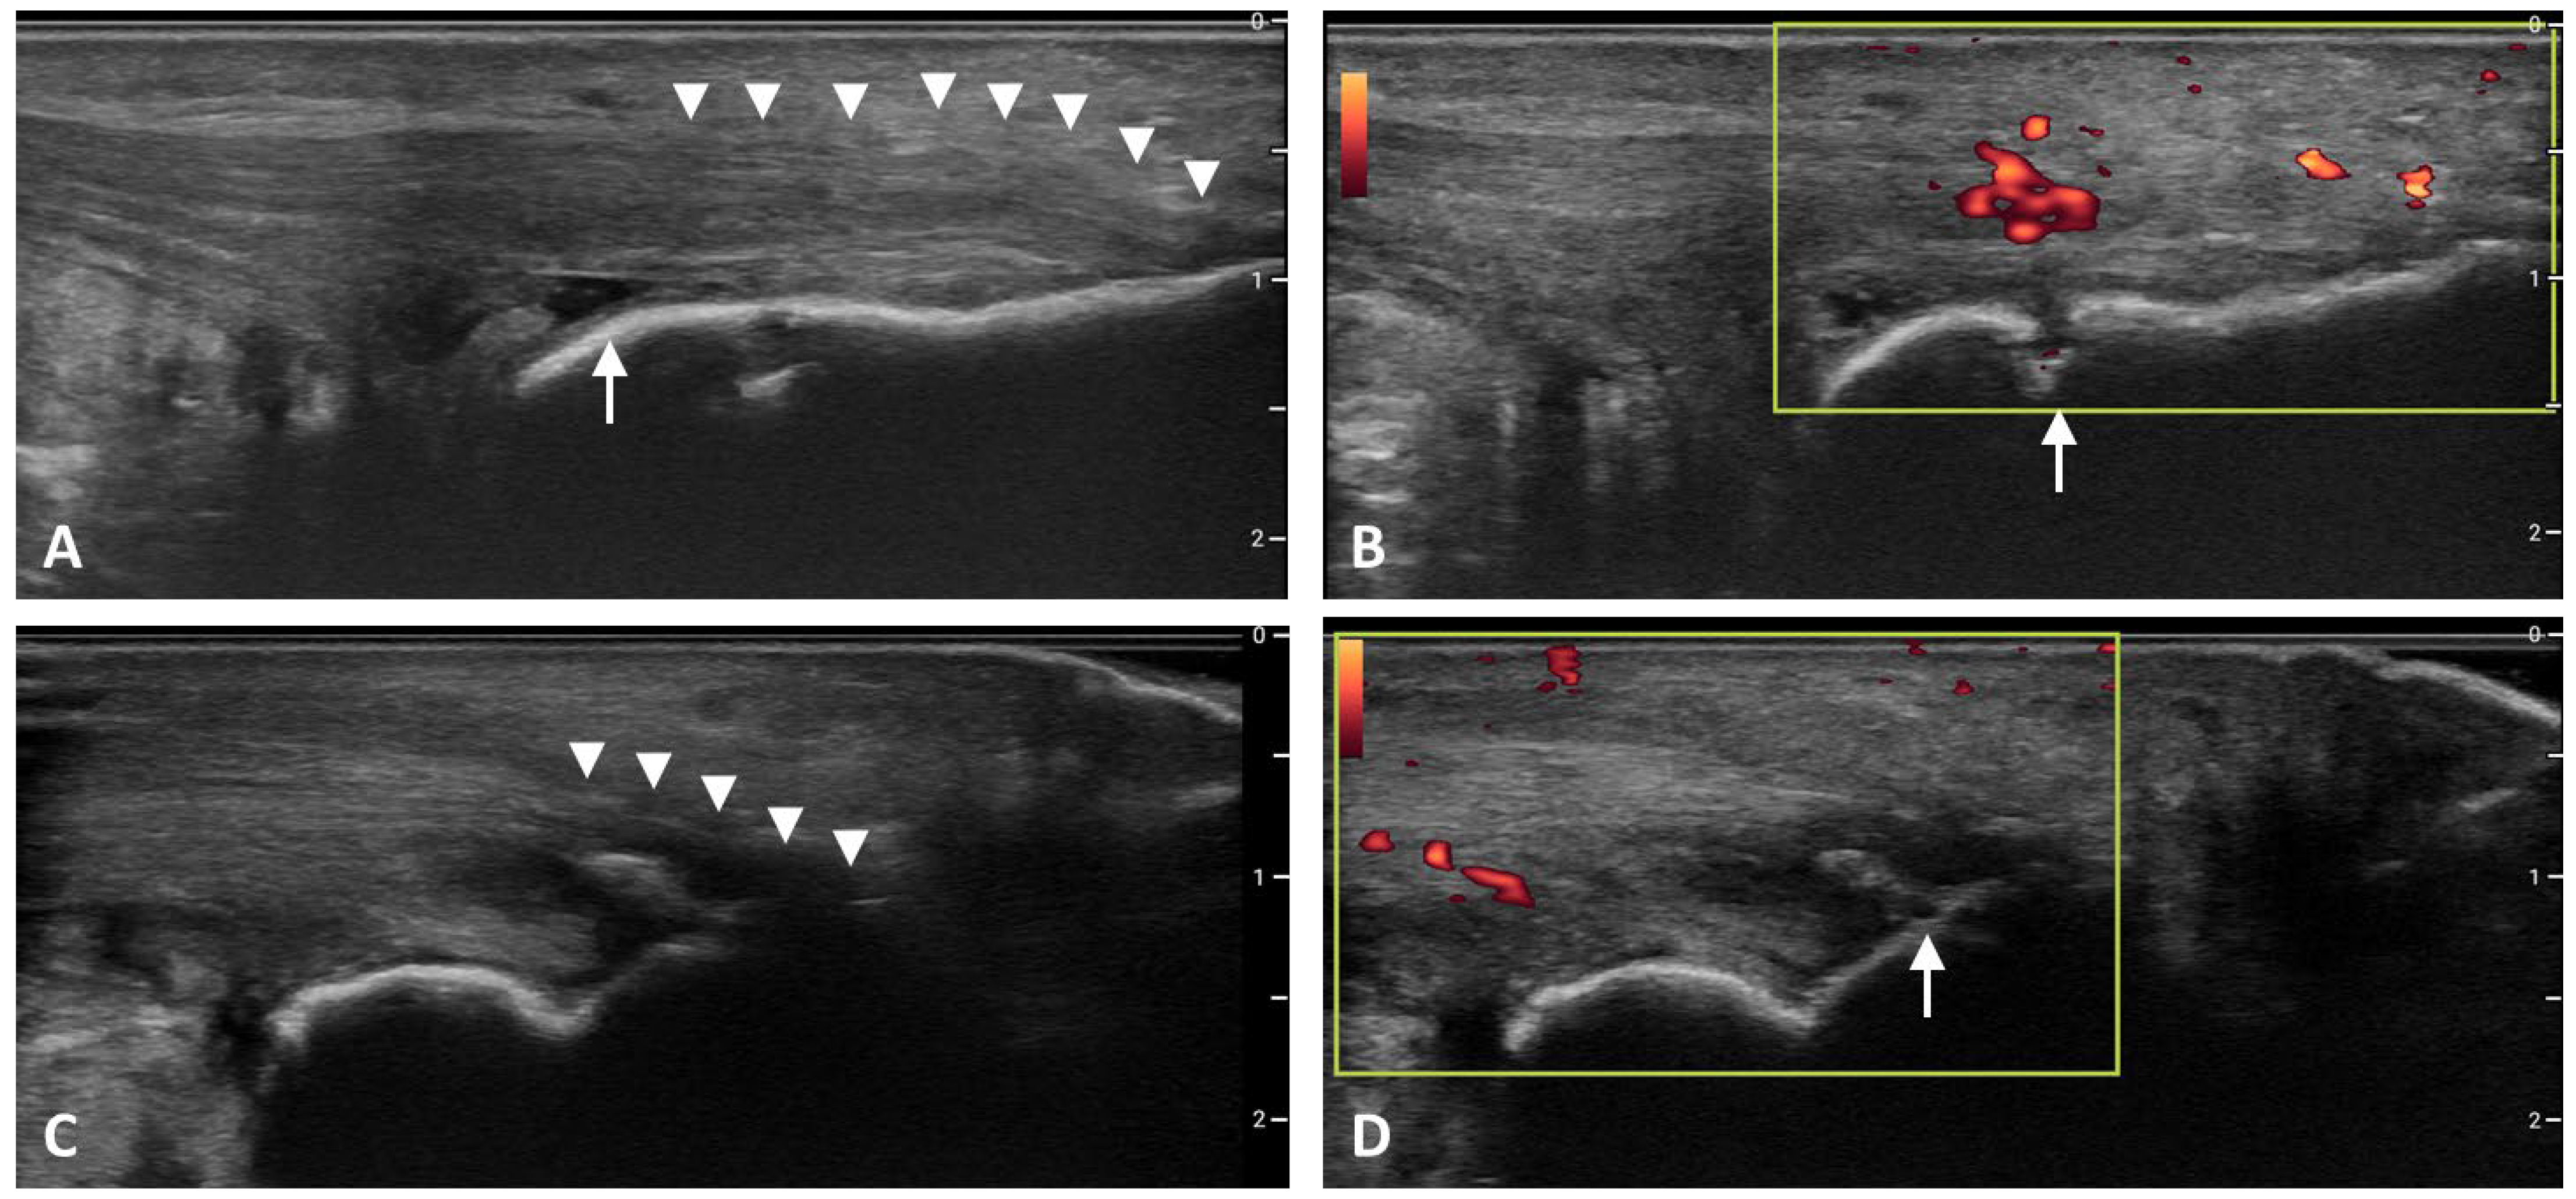

In 2018, Balint and D’Agostino collaborated through the OMERACT Ultrasound Task Force to develop a consensus-based definition of enthesitis as detected by ultrasound. In this endeavor, bursitis and tendinitis as detected by PD were discussed but ultimately believed to be separate findings that were not considered sine qua non for the detection of enthesitis, but rather as secondary findings that may be observed when inflammation has extended beyond the anatomic enthesis [6]. In addition to providing a framework for the development of an ultrasound definition for enthesitis, the OMERACT Task Force highlighted the need for future diagnostic ultrasound indices to utilize a weighted score for the severity of detected gray scale and PD abnormalities [6]. Characteristic sonographic features of enthesitis are shown in Figure 2.

Figure 2. Ultrasound Findings in Enthesitis. (A). Entheseal thickening (arrowheads) and retrocalcaneal bursitis (arrow). (B). Power Doppler signal adjacent to entheseal insertion and erosion (arrow). (C). Hypoechogenicity (arrowheads). (D). Enthesophyte/calcification. Images of Achilles enthesitis in gray scale and power Doppler.